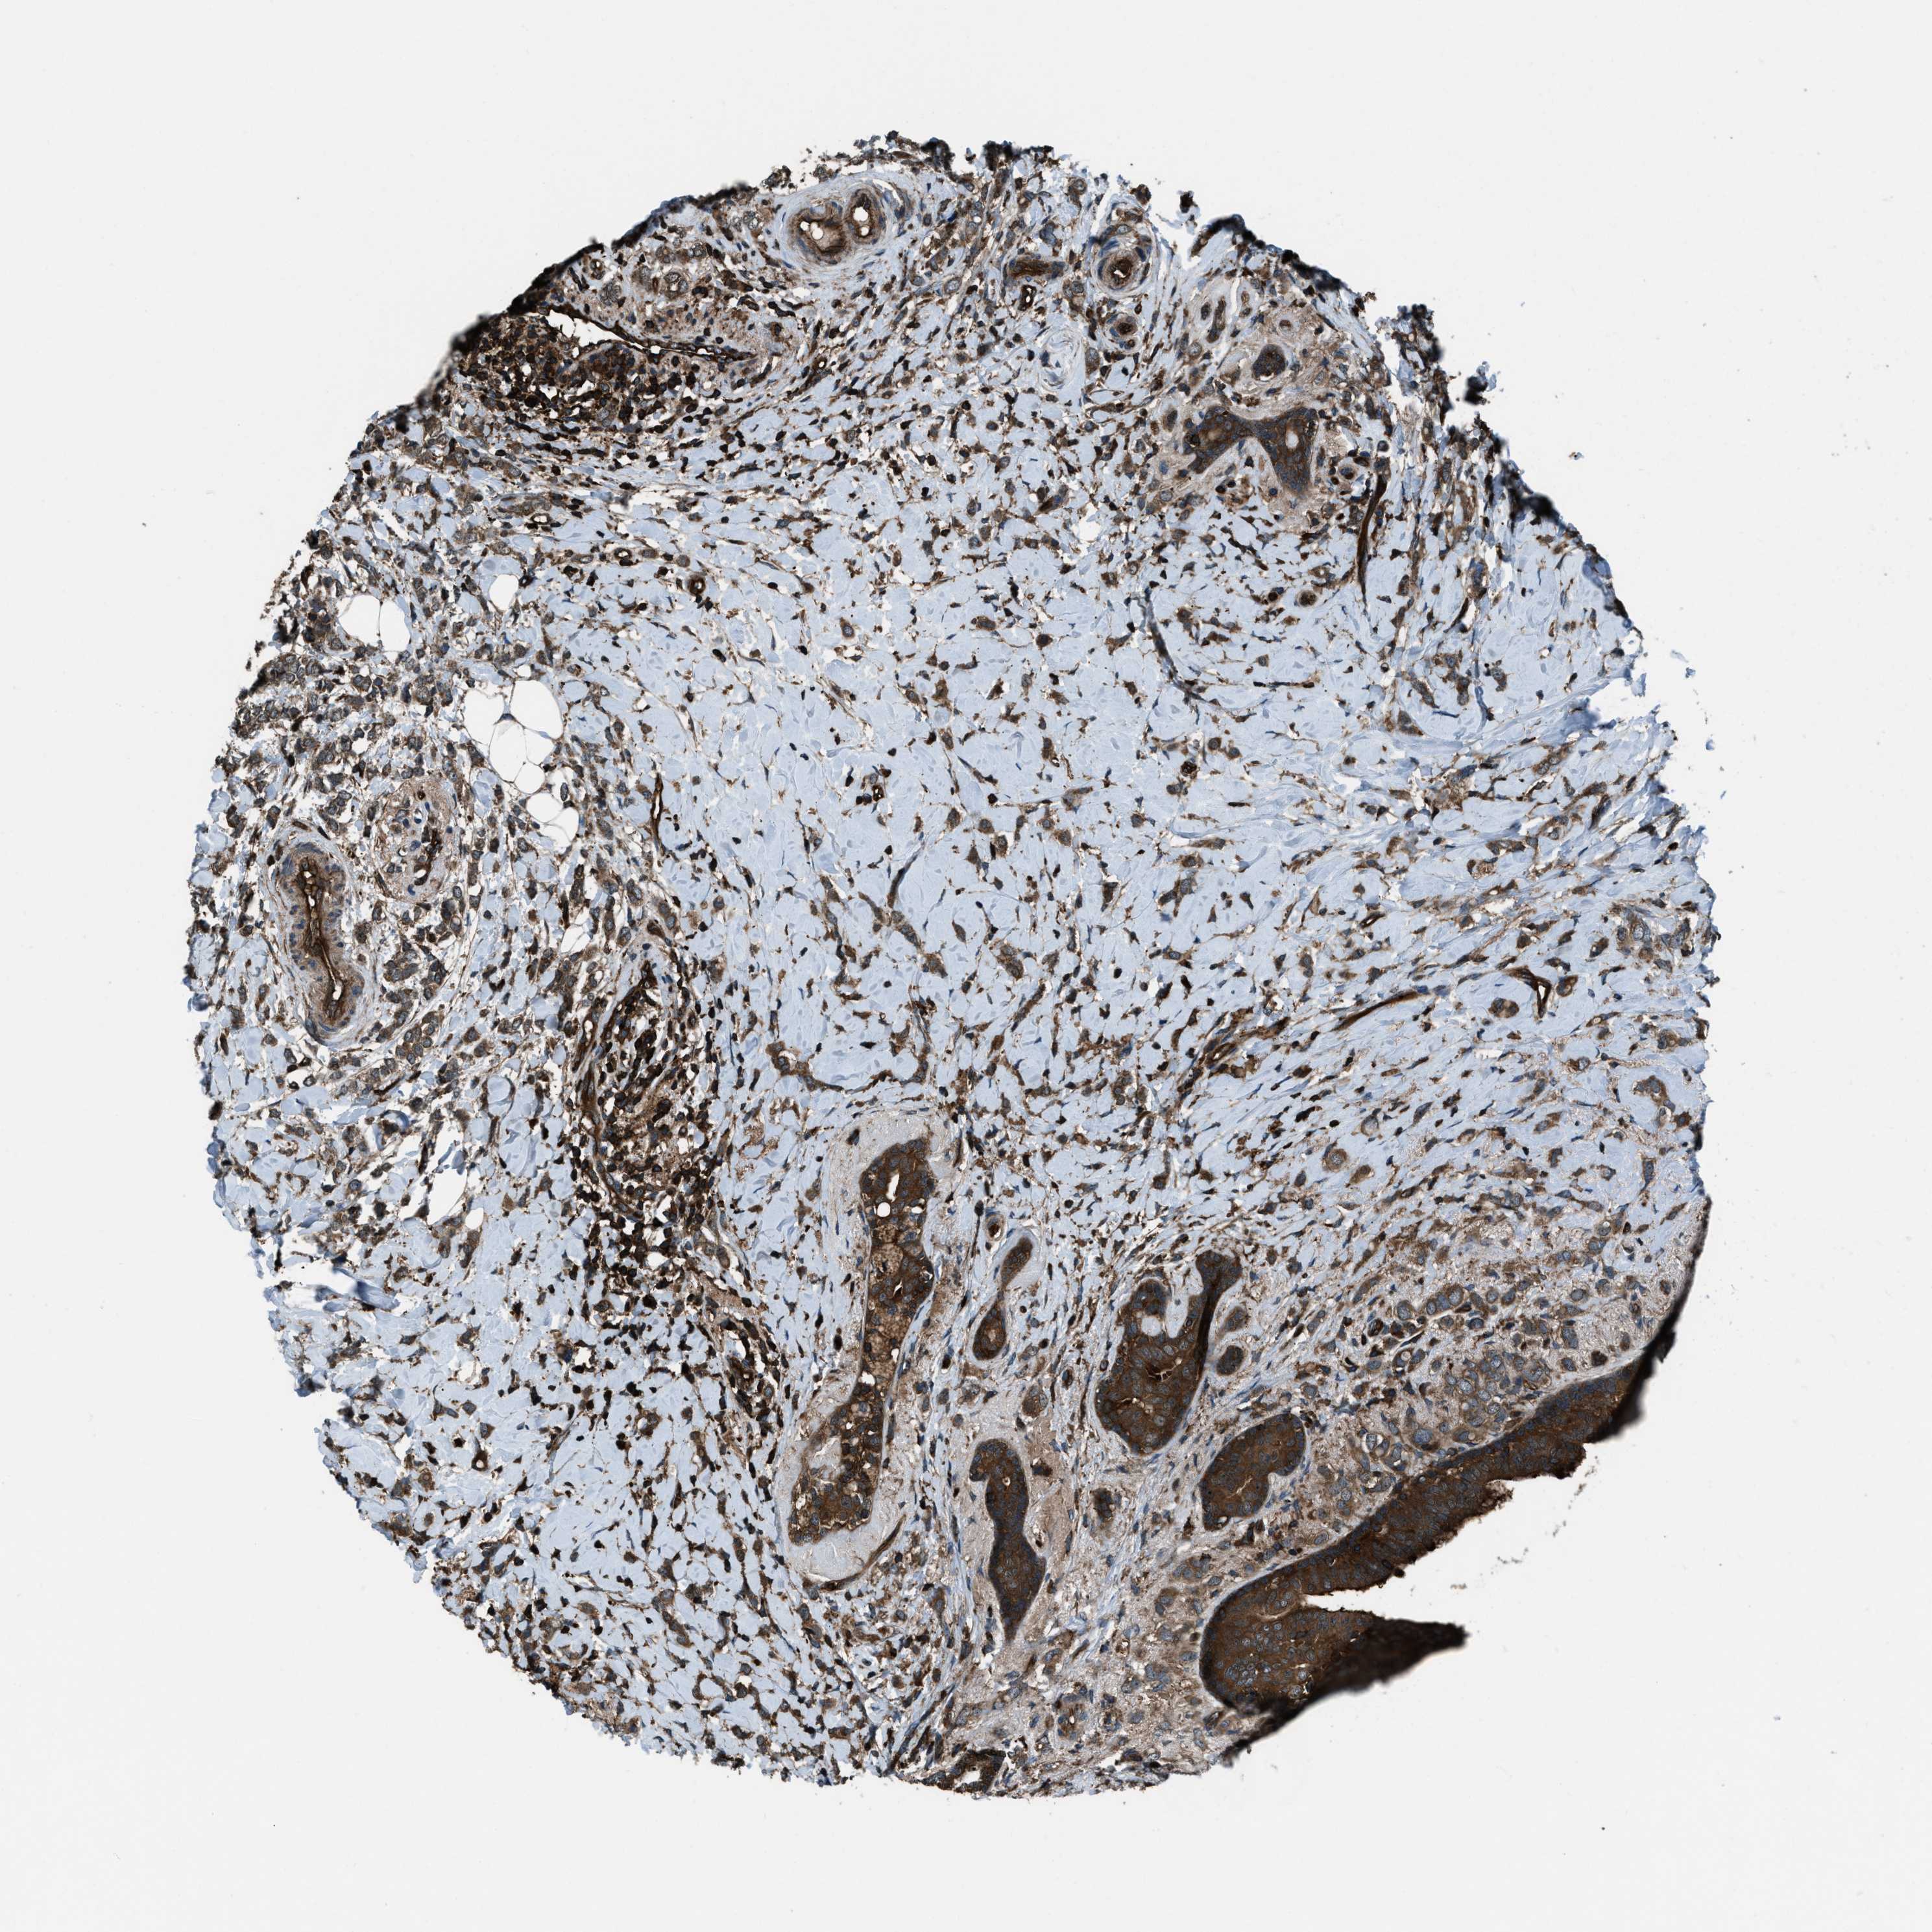

CANCER BREAST CANCER Show tissue menu

BRCA TCGA BRCA VALIDATION PROTEIN EXPRESSION